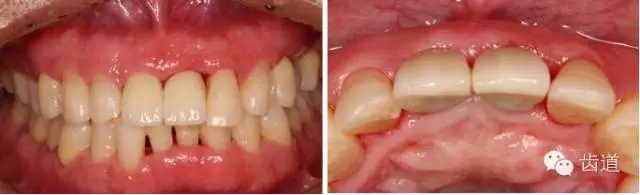

戴牙半年后復(fù)查

戴牙一年前后對(duì)比